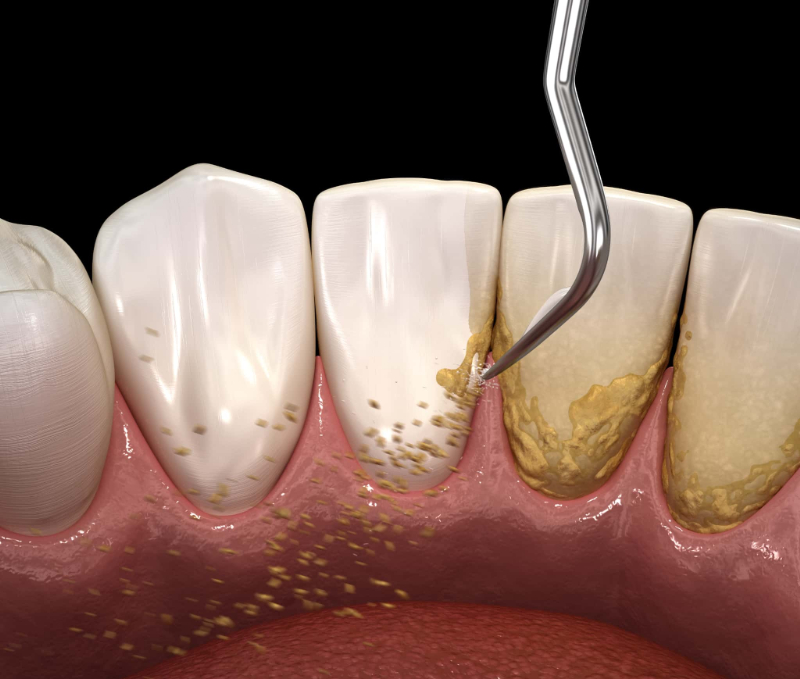

どのような歯周病の状態でも、まずは歯周基本治療から行います。歯周基本治療とは、歯周病の進行を食い止めるために行う治療です。歯周基本治療では、主にスケーリングとルートプレーニング、ブラッシング指導を行います。

スケーリングは、歯にこびりついている歯垢・歯石を除去する処置です。ルートプレーニングとは、歯の根の部分を滑らかにして歯石が付着するのを防ぐための処置です。これらは同時に行われることも多いです。

歯周病治療においては口内のプラーク(歯垢)や歯石を減らし、細菌数を減らしていくことが重要ですが、そのためには患者さま自身のセルフケアも欠かせません。そのため、ブラッシング指導も実施するのが一般的です。